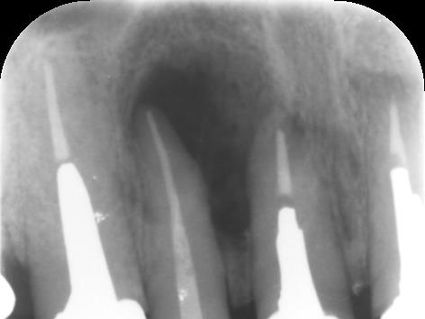

根分岐部側に広範囲なストリッピングパーフォレーションが確認できる。

根尖側にも湾曲根管を直進してできたパーフォレーションがある。

他院にて根管治療中の方で、根管治療が終わったのに痛みとサイナストラクト(旧フィステル)が

無くならないとのことで来院

手前側の1根管だけで2ヶ所のパーフォレーションがあり、MTAにて根管充填がされていた。

MTAを全て除去し、通法に従い根管治療後、MTAにて根管充填を行なった。

根管充填後、既にエックス線上にて病変の縮小を認めた。